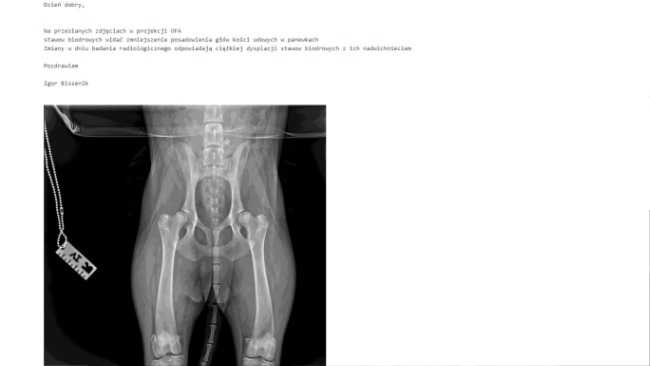

Miesiąc temu zdiagnozowano u niej chorobę genetyczną- dysplazję. Operacja nie należy do trudnych, jednak sukces leczenia zależy od szybkości jej podjęcia. Ostatni termin, w którym można wykonać skuteczną operację to 17.02.2022 r.

Karelski pies na niedźwiedzie to rasa pierwotna, dla której podstawą jest aktywność ruchowa. Choroba uniemożliwia bieganie Furii, powoduje niesprawność tylnych łap i ból. Przeniesienie całego ciężaru na przednie łapy doprowadziło do utworzenia przerostów na przednich kończynach. Pies aktualnie przyjmuje środki przeciwbólowe.